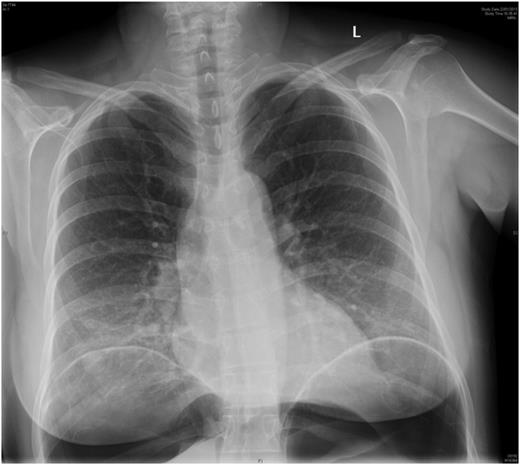

The patient failed to have a return of normal bowel function post-decompression and after 3 days was administered 500 µg of neostigmine via subcutaneous injection in an attempt to improve bowel motility. That evening she developed fever, and abdominal pain and erect chest X-ray confirmed free gas under her diaphragms (Fig. 3). She was taken to theatre for emergency laparotomy. At operation she was found to have two sites of caecal perforation with a moderate faecal contamination in the right paracolic gutter. A right hemicolectomy with primary anastomosis was performed. She was discharged home on post-operative Day 7 without further complication. It is possible that the serosal tears of the caecum had occurred secondary to either administration of neostigmine or dilatation in the post-Caesarean period.